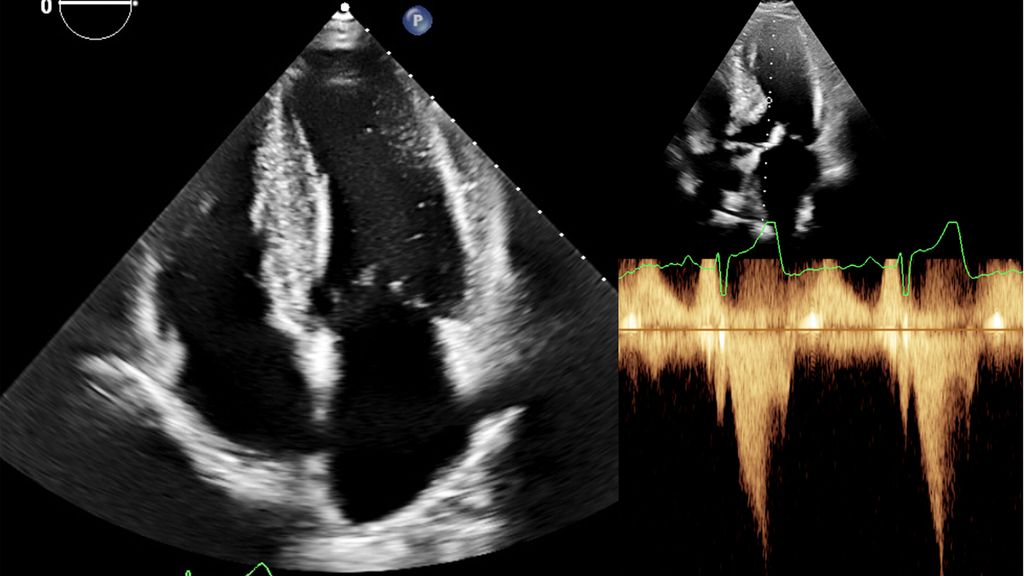

Zur echokardiografischen Beurteilung einer LVH wird üblicherweise der Durchmesser des intraventrikulären Septums und der Posterolateralwand herangezogen. Hier gelten bereits Werte >9mm bei Frauen und >10mm bei Männern als verdickt. Methodenbedingt werden die Wanddicken in der Echokardiografie jedoch häufig überschätzt (Abb.2). Definiert ist die LVH deshalb über die myokardiale Masse bezogen auf die Körperoberfläche (BSA; w: ≤95g/BSA; m: ≤115g/BSA), einen Parameter, der in der klinischen Praxis kaum verwendet wird.8

Abb. 2: Echokardiografie bei HOCM mit 4-Kammer-Blick (links) und Obstruktion im Ausflusstrakt (rechts)

Dennoch ist die Echokardiografie aufgrund der niederschwelligen Verfügbarkeit als erste Untersuchungsmodalität und zur Verlaufsbeurteilung nicht wegzudenken. Mit der Ejektionsfraktion, der Vorhofgröße und der Beurteilung der diastolischen Funktion können prognostisch wichtige Parameter erhoben werden. Ein „apical sparing“ in der Analyse des myokardialen Strains oder der Aspekt eines „granular sparkling“ kann einen Verdacht auf kardiale Amyloidose begründen (Abb.3). Jede echokardiografische Untersuchung wegen des Verdachts auf LVH sollte außerdem eine Bestimmung des LVOT-Gradienten inkl. Valsalva-Manöver beinhalten (Abb.2).